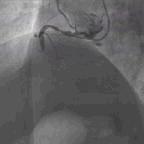

冠状动脉造影结果显示冠状动脉三支血管严重病变,左主干内膜不光滑但无狭窄,前降支开口狭窄95%,近段狭窄80%,D1内膜不光滑且近段狭窄80%,回旋支远段狭窄99%,OM1开口狭窄90%,OM2闭塞,右冠状动脉近段狭窄60%~80%,中段闭塞(图2)。SYNTAX评分46分。

图2. 冠状动脉造影